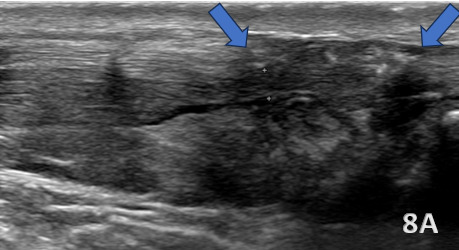

ACHILLES TENDON TEAR

Figure 8A (LAX View):

Achilles tendon tears most commonly occur 2–6 cm proximal to the calcaneal insertion, a region of reduced vascularity. On diagnostic ultrasound, full-thickness tears (highlighted with the blue arrows) appear as discontinuities in tendon fibers with a hypoechoic or anechoic gap, while partial tears (<50% disruption) demonstrate focal hypoechoic areas with some intact fibers. Fluid and debris are often visible in Kager’s fat pad, accompanied by mild hyperemia on Doppler imaging. Bone fragments may be present near the insertion in cases of avulsion injuries, and portions of the tendon may remain intact even with significant disruption. The Kuwada classification system categorizes tears: Grade I (partial rupture, <50%), Grade II (complete rupture, gap <3 cm), Grade III (gap 3–6 cm), and Grade IV (gap >6 cm). Dynamic imaging during dorsiflexion and plantarflexion confirms tendon discontinuity and retraction, guiding diagnosis and management.